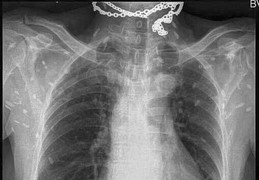

Một bé gái 8 tuổi bị đau đầu tê liệt, co giật và lên cơn động kinh, sau khi nhập viện cả người nhà và bác sĩ đều sửng sốt khi phát hiện 100 trứng sán dây trong não cô bé.